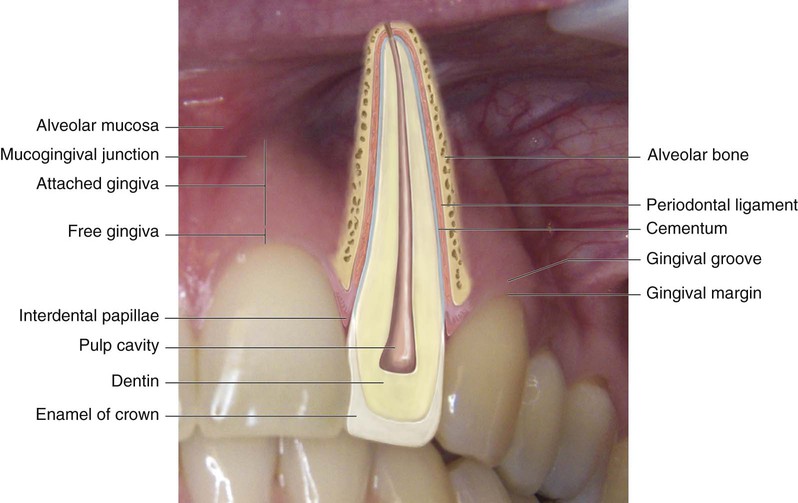

Periodontal disease is an infectious disease process that involves inflammation of the structures of the periodontium (Table 14-1). The periodontium is made up of structures that surround, support, and are attached to the teeth (Fig. 14-1). Periodontal disease causes a breakdown of the periodontium, resulting in loss of tissue attachment and destruction of alveolar bone.

Structures of the Periodontium

| Name | Description |

| Gingivae | Commonly referred to as gums. This mucosa covers the alveolar process of the jaws and surrounds the necks of the teeth. |

| Epithelial attachment | Tissue at the base of the sulcus where the gingiva attaches to the tooth. |

| Sulcus | Space between the tooth and the free gingiva. |

| Periodontal ligaments | Dense connective fibers that connect the cementum covering the root of the tooth with the alveolar bone of the socket wall. |

| Cementum | Covers the root of the tooth. The primary function of the cementum is to anchor the tooth to the bony socket with attachments of the periodontal ligaments. |

| Alveolar bone | Bone that supports the tooth in its position within the jaw. The alveolar socket is the cavity in the bone that surrounds the tooth. |

From Robinson D, Bird D: Essentials of dental assisting, ed 4, St Louis, 2007, Saunders.